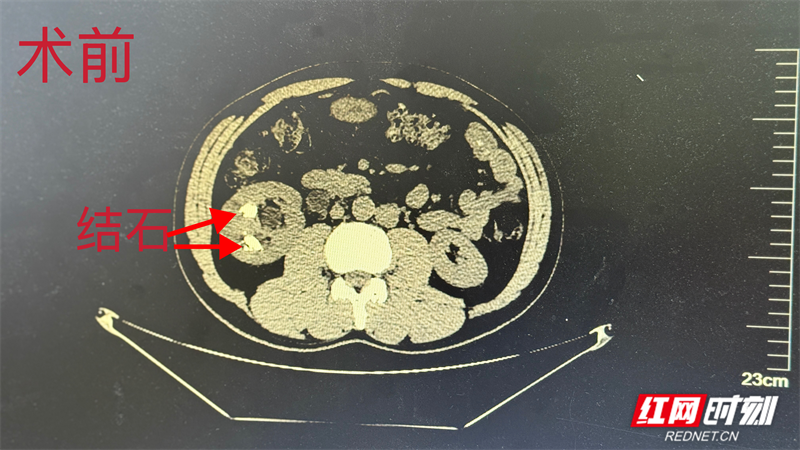

李某被肾结石困扰多年,曾多次行结石手术,但反复发作的钝痛与不适感长期困扰着他的生活和工作。经过反复咨询与比较,他最终将希望寄托在湘南地区的郴州市第四人民医院泌尿外科。面对患者的信任,泌尿外科主任陈星星接诊后,针对其肾脏内结石的位置与大小,决定采用常规开展的输尿管软镜钬激光碎石术为患者解除病痛,通过人体自然腔道精准碎石。同时,结合科室成熟的加速康复护理模式,从术前指导到术后康复,全程精准护航。